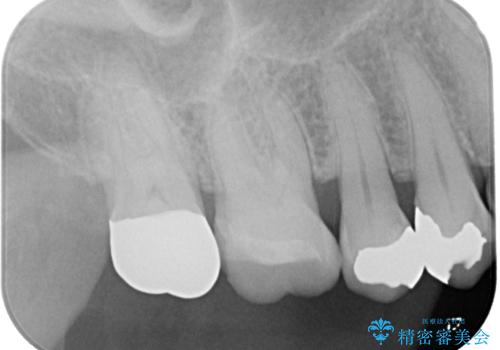

歯と歯茎の間に圧排糸と言われる糸を入れてシリコーン印象材にて精密な型どりをしました。

ハイブリッドインレーの装着時には、唾液の侵入を防ぐために、ラバーダム防湿を行いました。

見ため、機能面ともに違和感なく大変喜んでいただきました。